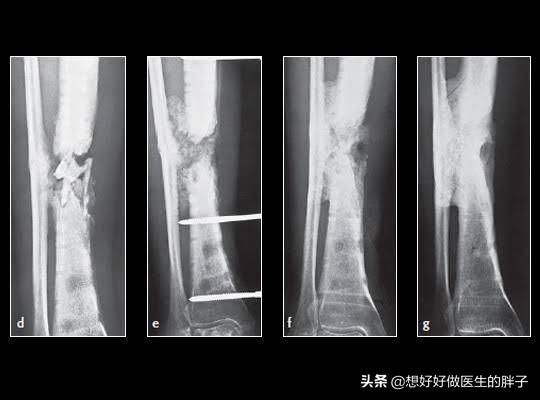

第一,一定要去复查骨折x线的情况,是否有明显的骨不连,也就是骨折没有愈合,骨折之间还存在着明显的松动,这样在活动的时候就会刺激骨折周边软组织等结构,导致肿胀不消退。另外七个月的时间,如果是手术治疗,是否存在折端的感染,在x线上也会有体现,长期的慢性感染也会导致肢体的肿胀,而且患者不一定会有明显发热等症状。

●如果存在骨不连的情况,7个月的时间对于胫腓骨粉碎骨折来说还不能说没有愈合的希望,因为这个位置由于其特有的血供特点,一旦骨折愈合就会比较慢,可以尝试去当地医院进行冲击波治疗,尤其是聚焦式冲击波治疗,对于骨不连有比较好的治疗效果,不需要2次开刀就有促进骨折愈合的疗效。目前有研究数据显示冲击波治疗骨不连有70%左右的愈合几率,所以建议还是先进行保守治疗三个月无效再考虑开刀手术治疗骨不连。而骨头愈合了,下肢稳定了,肿胀也就慢慢消退了!

●而如果存在慢性骨髓炎,这种情况导致的下肢肿胀,可能需要根据具体情况选择保守还是手术治疗了。

胫腓骨这个位置一旦发生骨折,愈合也比较慢,肿胀消退比较慢,因为这个位置血运相对来讲不是特别的好,即使是体重比较大的人在小腿这个部位也是比较细的,尤其是在胫骨前方这个部位,一般都是皮包着骨头,一旦发生骨折恢复起来比较慢,也是可以理解的!但是7个月的时间如果仍然明显肿胀的话,一定要进行x线的检查以及下肢血管彩超的检查,明确是否有骨不连、骨折的感染或者是下肢血运的问问题。如果检查没有太大的问题,建议要科学的康复锻炼,同时平时注意减少下垂下肢的时间,可以口服一些促进肿胀消退的药物。